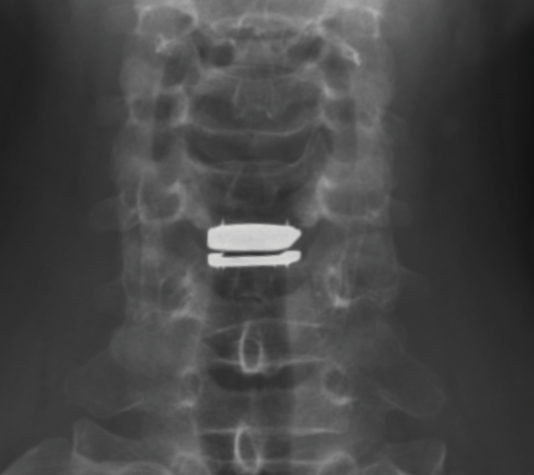

This patient is a 36-year-old male with a history of neck pain radiating into both shoulders, numbness in radial 3 fingers of both hands. The onset was after he hit an open car while riding his bike, flipped over the handlebars, and hit his head. He was treated conservatively for a year with physical therapy and pain management.

His MRI demonstrated disc herniation at C5-6 without adjacent segment pathology. The herniation level corresponded to his radicular distribution (C6).

I planned pre-operatively to use prodisc C Vivo and therefore during surgery I did not use my usual drill carpentry on the upper endplate and left it intact convex. Trialing was critical–he is 6’5” tall so I started with a 6mm tall XL Deep trial and I felt this fit perfectly. The trial was easily moveable but not loose. The facet joint gapping matched that of the adjacent segments. I was able to place the dome within the endplate with a perfect match while also achieving perfect placement of the center of rotation. I honestly walked out of this case thinking how much I love prodisc C Vivo since it fits so perfectly.

Implant selection was a critical pre-operative consideration. This patient is a young athletic person, so I wanted to use a device with proven core longevity and biomechanics. Preoperative considerations included measuring his disc on the preop MRI – at 20mm deep, this excluded several implants that only make a 16mm deep footprint.

In addition, since he is 6’5” tall, I wanted a 7mm tall option available if needed; this also excluded some of my implant options. Finally, his superior endplate is concave, making an implant with a convex upper endplate an ideal fit.